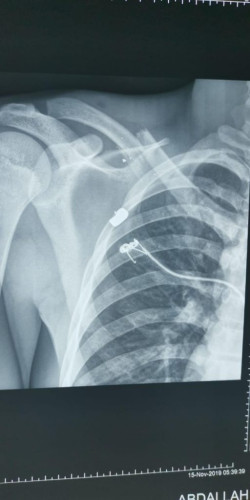

نجح فريق طبي في مستشفى القويعية العام، في اجراء اول عملية تثبيت كسر ترقوة مضاعف، وتعد الأولى من نوعها في المستشفى.